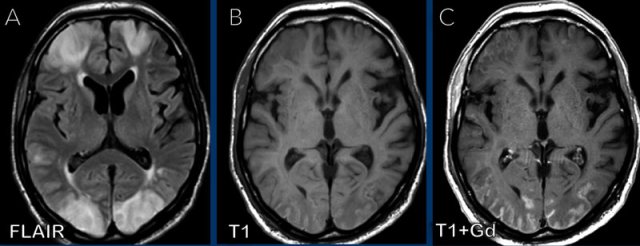

These images are of a 58 year-old male who presented with headache in the sitting and standing position.

Images

A

smooth dural enhancement is present in both the supratentorial and the infratentorial compartment.

Notice the small ventricles.

Continue with the sagittal images...

Image 1

The findings are rather subtle, but there is:

- Sagging of the midbrain with decreased pontomamillary distance, effacement of the suprasellar cistern, flattening of the anterior pons and kinking at the craniocervical junction.

- The hypothalamus is folding over the dorsum of the sella, the pituitary gland is somewhat enlarged (white circle).

- The interthalamic substance is lowered; the posterior part of the corpus callosum is lowered (‘drooping penis sign”). Note the flattening of the supracerebellar cistern.

- In this case the tonsils are in a normal position and there is no herniation (yellow circle).

Conclusion: findings

typical for intracranial hypotension.